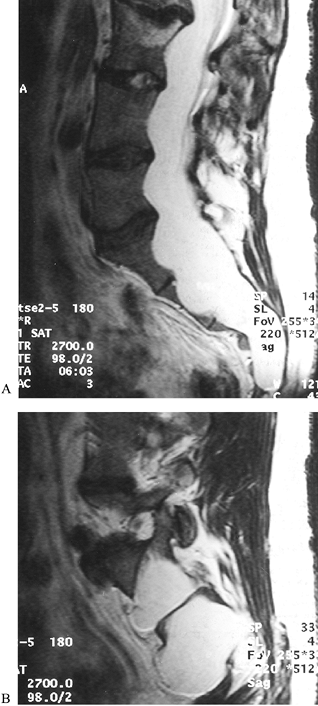

mind include the following: (a) The rate of dural ectasia is high (63%)

in the lower lumbar or sacral canal (32) (Fig. 158.9).

![]() |

Figure 158.9.

CT scan without contrast shows dural ectasia with foramenal meningocele. This is common in Marfan syndrome, in the lower lumbar spine and sacrum. Exercise care if working inside the canal. Marked thinning of laminae may compromise fixation strength. |